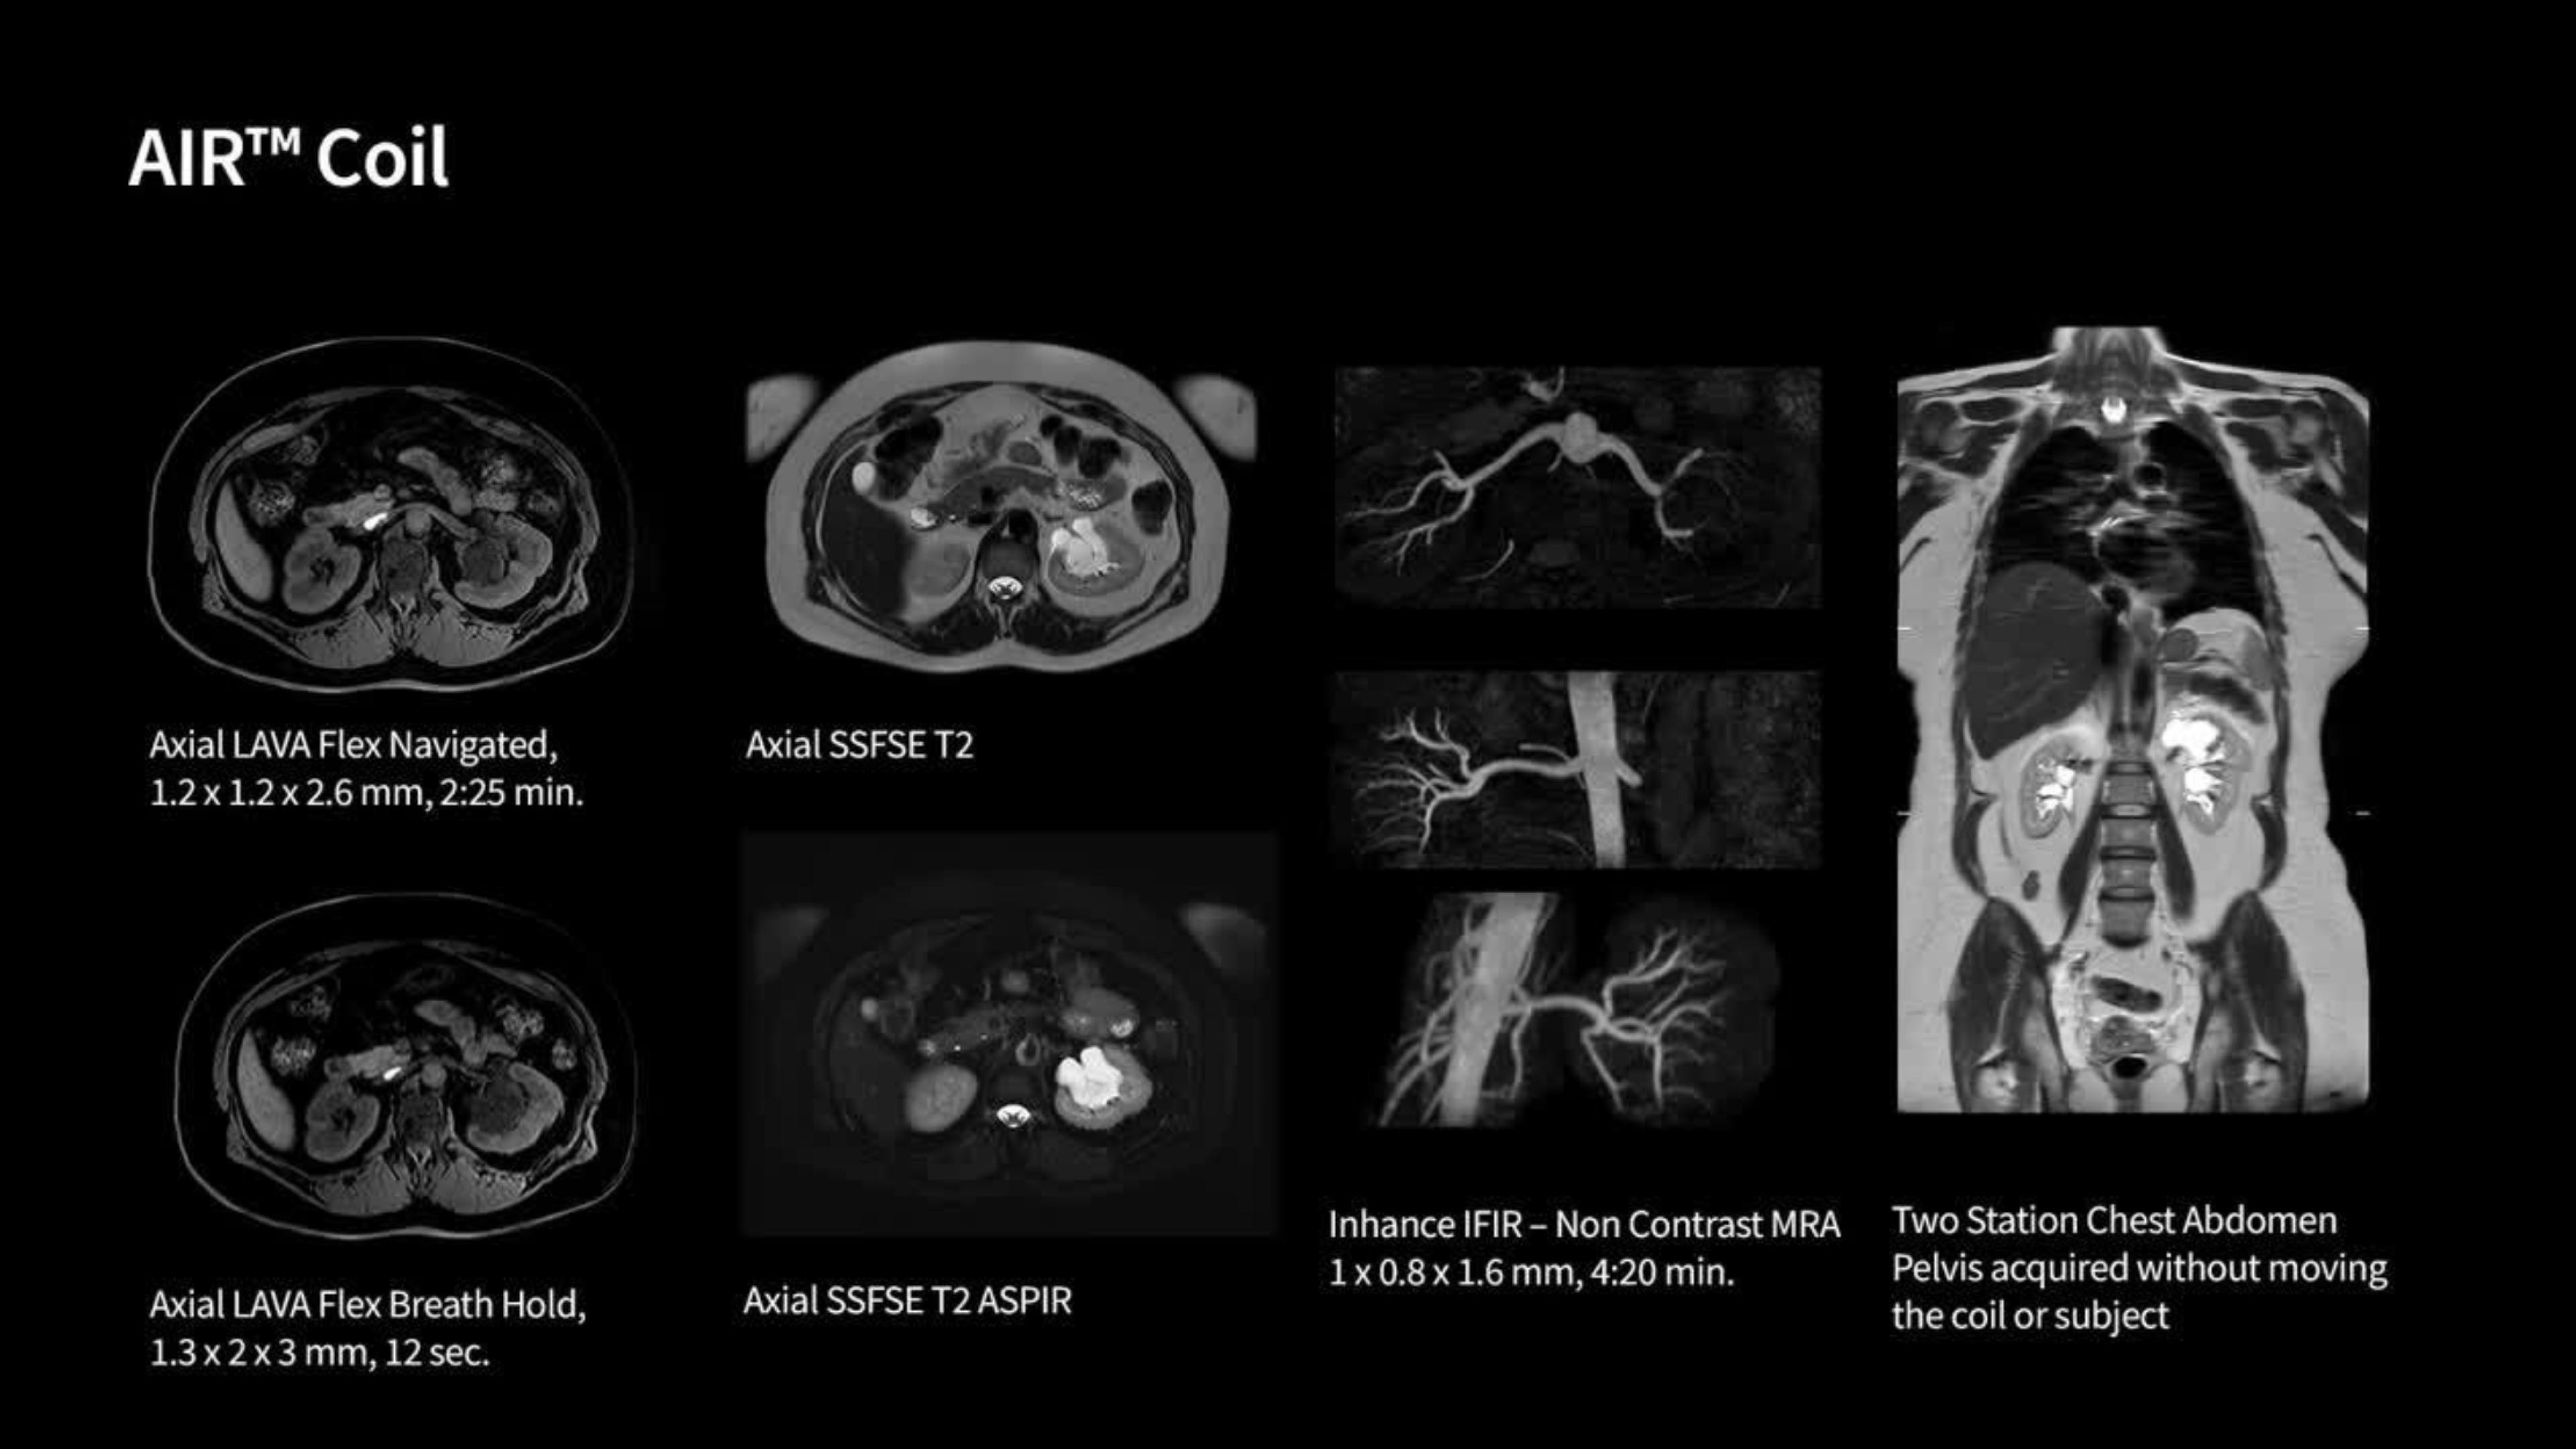

Feet-first imaging, AIR™ Coils for clinical versatility, and greater coverage